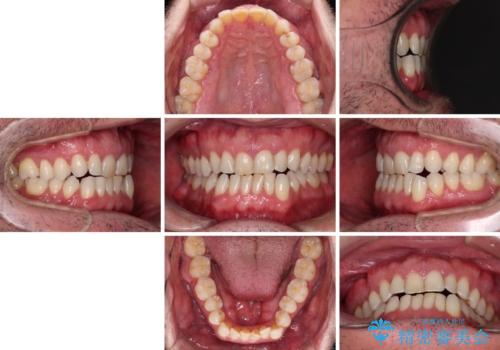

- 前歯でものを噛みきりたいとのことで来院された患者様です。

以前矯正治療を経験されたそうですが、舌の突出癖により上下前歯に隙間ができている様子でした。

前歯の非接触改善は、インビザラインの得意とするところですが、マウスピース矯正は絶対に継続できないとのことで、ワイヤー装置にて矯正治療を行うこととしました。